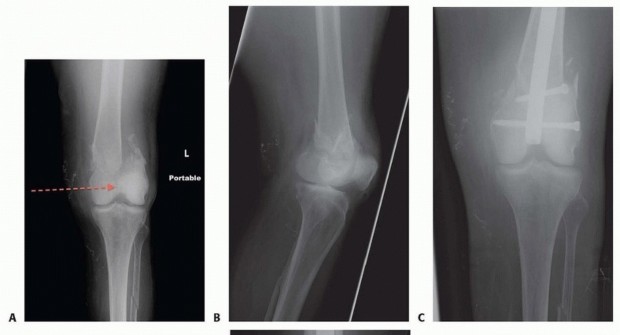

### FIG 9 • Critically ill elderly polytrauma Jehovah's witness patient with left C1 distal femur fracture. A,B. Initial injury AP and lateral views. C,D. Due to extremely low hematocrit, external fixation was the only surgical option allowed to minimize blood loss. Radiographs in bridging external fixation. The AP shows excellent alignment but the lateral shows the expected extension deformity secondary to pull of gastrocsoleus complex. E,F. After 5 weeks in an external fixator, AP and lateral radiographs show callus formation (red arrows). Patient is now cleared for definitive surgical intervention. Antegrade intramedullary nailing has been described and can be used for distal fractures with a large enough distal segment to allow for two locking screws. Malalignment has been a problem, as has adequate fixation. 4, 8 Retrograde intramedullary nailing can be used in the following cases ( FIG 10): All extra-articular type A fractures greater than 4 cm from the joint. This minimal length of the distal femur allows for multiplanar interlocking in the distal fragment. Type C1 or C2 fractures where the articular fracture can be anatomically reduced closed or with limited exposure. Percutaneous screws are used for the articular injury. Periprosthetic fractures around a total knee arthroplasty with an “open box” femoral component Most surgeons prefer to use a long nail, but short supracondylar nails are available as well. Multiple-hole short supracondylar nails have fallen out of favor. Plate fixation ORIF with plates can be used for all types A and C fractures but is ideal for the following injuries: Very distal type A fractures within 4 cm of the knee joint All articular type C fractures, but always for C3 types Periprosthetic fractures about a “closed box” femoral component of a total knee arthroplasty The partial articular type B1 or B2 if an antiglide plate is needed Plate options (preferred to least preferred; fixed-angle devices preferred) Fixed-angle locking plates (percutaneous jigs are advantageous and allow for minimally invasive techniques) Variable-angle (polyaxial) locking plates—allow for “fixed variable locking” within a defined range. It is useful for distal fractures and allows for increased screw 473 trajectories to gain additional locked fixation in short segments, which may not be feasible with fixed-angle trajectory plates ( FIG 11).

### FIG 10 • A,B. AP and lateral radiographs of an elderly patient with multiple comorbidities with an extra-articular distal femur fracture (AO type A; an incomplete intercondylar split— red dashed arrow). C,D. Postoperative radiographs showing stabilization with retrograde intramedullary nail. E,F. One-year postoperative radiographs showing a healed fracture with some subsidence of the metaphyseal region and mild protrusion of hardware through the notch. Ninety-five-degree condylar screw Ninety-five-degree blade plate Nonlocking plates with or without medial support (medial plate or external fixation) Limited internal fixation Limited fixation with screws only can be used for partial articular type B, especially type B3. The amount of open reduction required depends on the adequacy of closed reduction techniques and obtaining an anatomic reduction of the joint surface. Headless screws are useful for type B3 fractures in which the screws have to penetrate the joint surface ( FIG 12). Countersinking the screw heads can also be performed. Biomechanics of fixation: implant considerations There has been concern that the newer locking plate constructs are too stiff, resulting in inconsistent and asymmetric callus formation. 9 Some clinical evidence show less callus formation with stainless steel plates versus titanium plates. 9 Conversely, a biomechanical study has not shown a significant difference mechanically between constructs of stainless steel LISS plates with bicortical screws or titanium LISS plate with unicortical screws.1 474